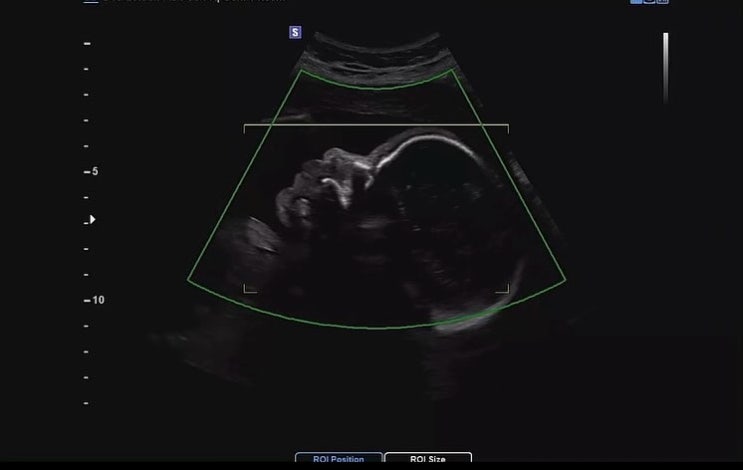

찰떡이 이야기

하하, 조금 민망하지만 우리 건강찰떡이를 소개합니다?? 결혼 8년 차, 8년이라는 결혼생활을 하며 울...